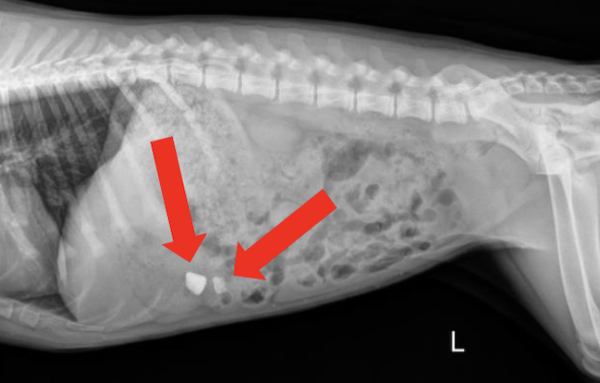

Radiograph findings:

The radiographs returned two radiopaque foreign materials in the stomach (shown above by the red arrows). These objects were suspected to be rocks. In order to confirm the location of these objects two views were taken including the lateral views above as well as a ventrodorsal (VD) view (not pictured).

Foreign bodies in the stomach. One large rock, and one smaller rock near the pylorus. The smaller rock was more concerning due to its location at the pylorus and the potential for it to become lodged at this location or pass into the duodenum.